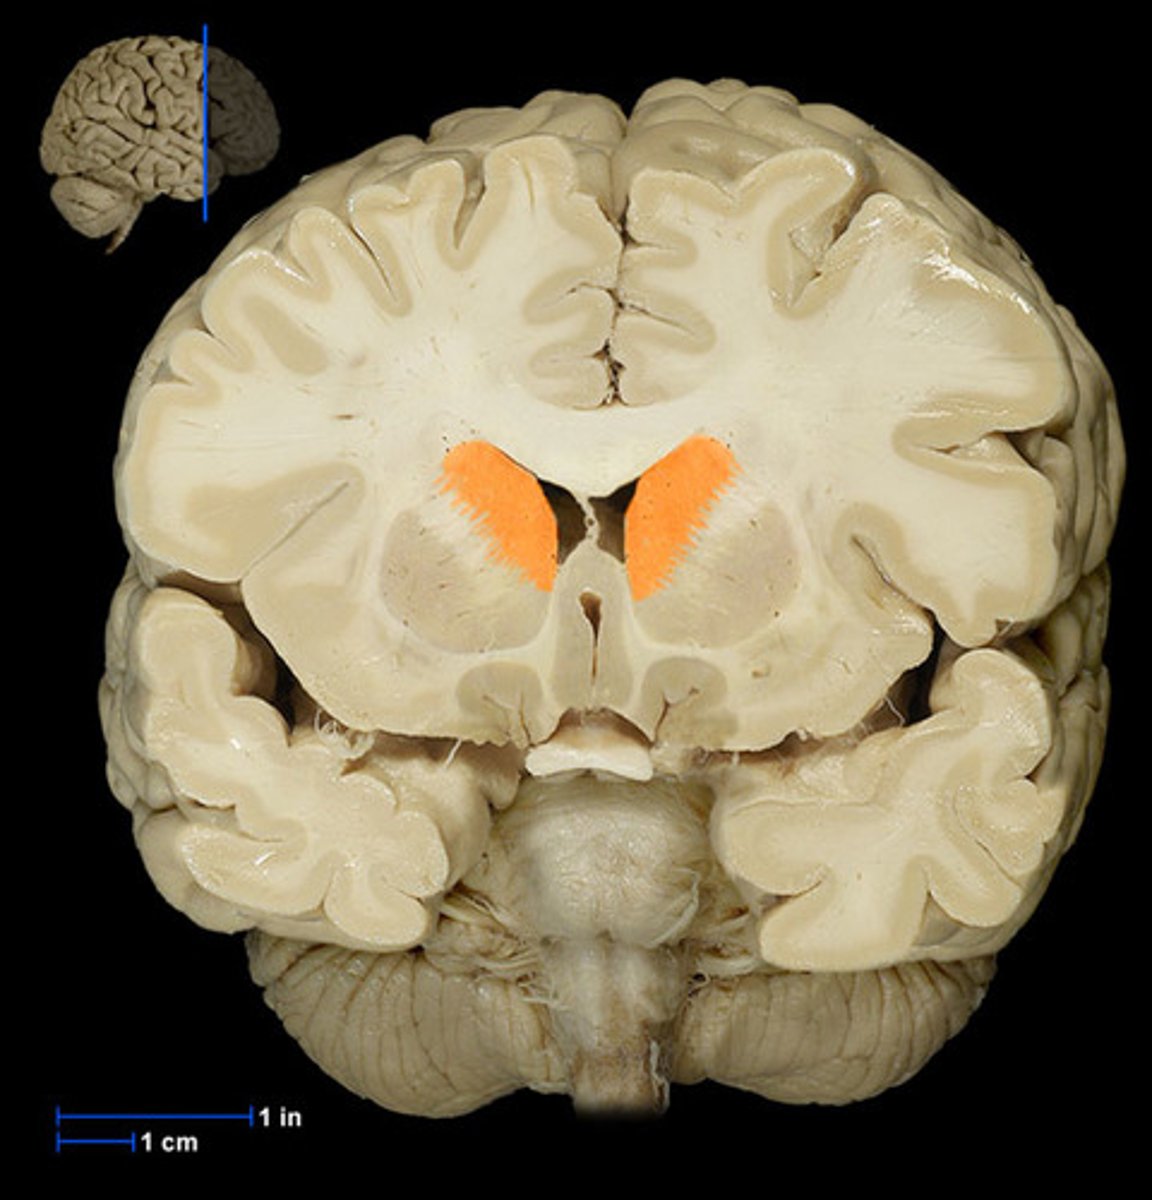

lateral ventricle

A complexly shaped lateral portion of the ventricular system within each hemisphere of the brain.

anterior horn of lateral ventricle

located in the frontal lobe and is the part of the lateral ventricle that lies in front of the interventricular foramen

body of lateral ventricles

located in the parietal lobe, situated between the anterior and posterior horns.

inferior horn of lateral ventricle

located in the temporal lobe of the brain. It is the largest of the three horns and extends from the atrium, curving anteriorly and inferiorly to go under the thalamus and into the temporal lobe

posterior horn of lateral ventricle

located in the occipital lobe of the brain, projecting backward. It is the most posterior part of the C-shaped lateral ventricle and lies deep within the occipital lobe.

interventricular foramen (of monro)

connects lateral ventricles to third ventricle

third ventricle

thin midline space that separates the left and right thalami.